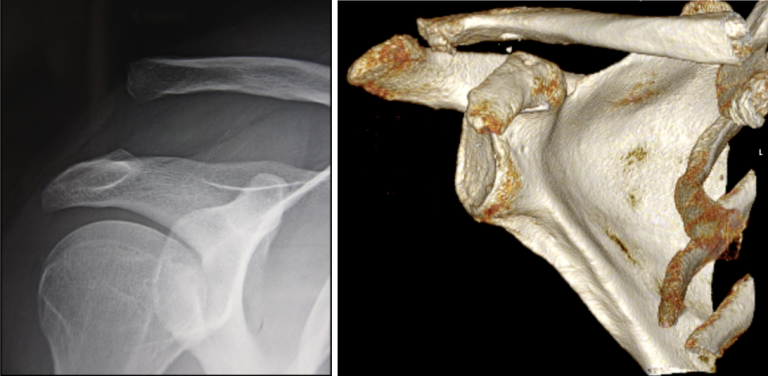

Le diagnostic implique un examen clinique où le médecin effectuera une palpation pour rechercher la douleur et évaluer la mobilité de l’articulation et de la clavicule. Des examens d’imagerie, tels que des radiographies de face et de profil, scanner, sont utilisés pour confirmer le diagnostic et évaluer la gravité de la luxation.

Le stade de gravité de la luxation (selon la classification de Rockwood) :

• Stades 1 et 2: Un traitement médical avec antalgiques et écharpe peut suffire.

• Stade 3: Une intervention chirurgicale est envisagée pour les cas complexes.

• Stades 4 à 6: Une intervention chirurgicale est nécessaire pour rétablir la mobilité de l’articulation.